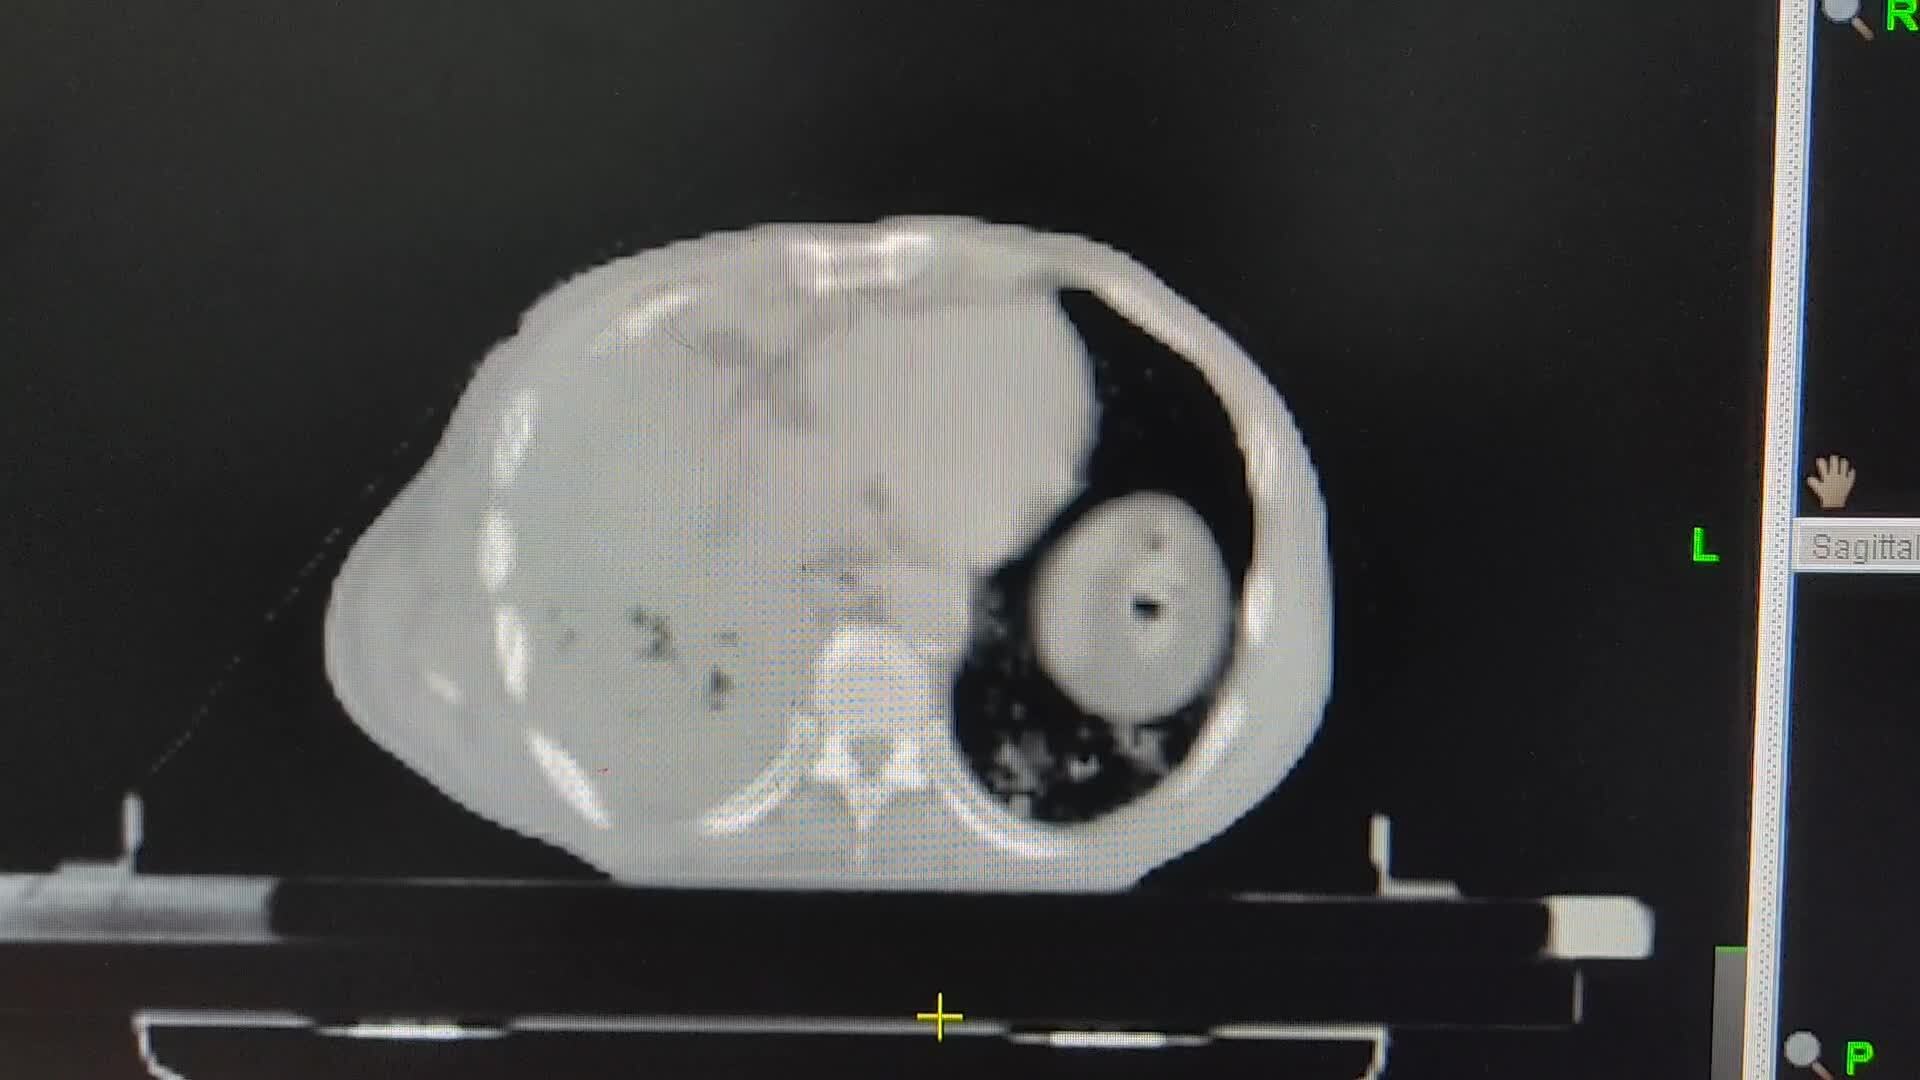

1例(男/74岁)膀胱癌多发转移(肺、骨、肝、脾、胸膜、纵隔、腹膜后、皮肤等)-TOMO放疗

郭某某(BS),男,74岁(出生时间:1949-02-01)

多模态图像融合(CTsim-PET融合):